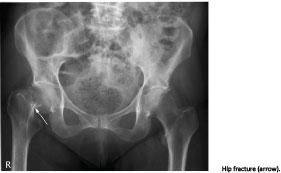

Hip fracture constitutes a worldwide public health problem among the elderly [1]. The most common cause of hip fractures is low-energy trauma combined with osteoporosis, and is most frequently seen in elderly women.